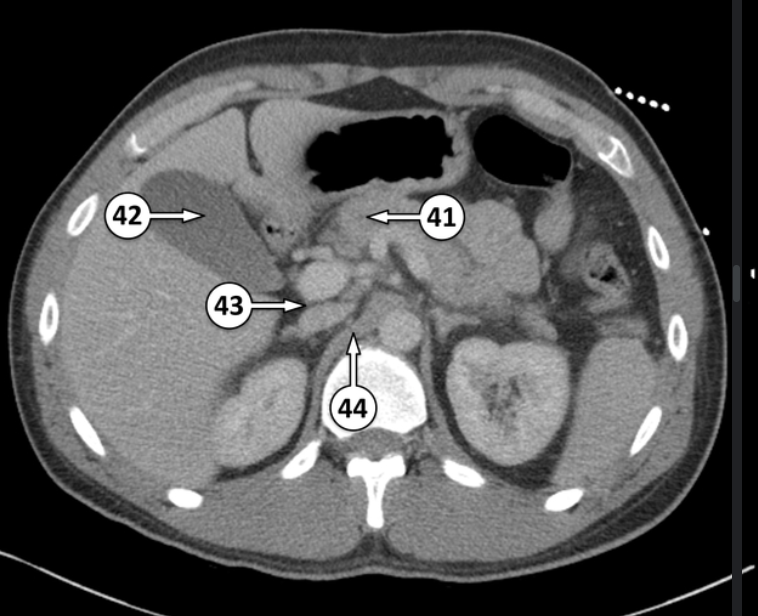

Label 41 and 42

main pancreatic duct

body of gallbladder